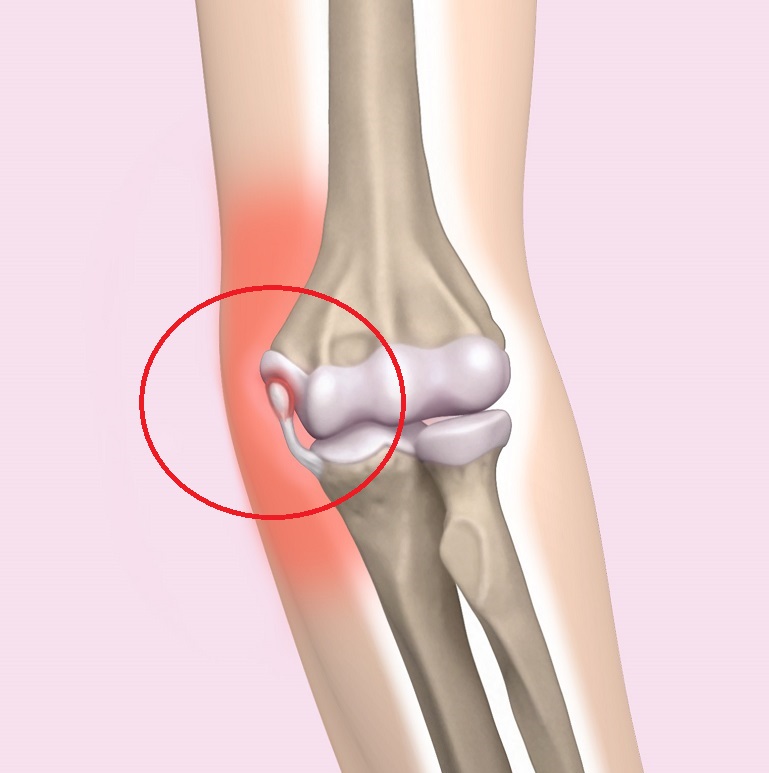

야구 엘보는 야구 투구, 특히 성장하는 투수에서 발생하는 과도한 사용으로 인해 발생하는 스포츠 장애로, 주로 내측 (그림 1), 외측 (사진 1)의 던지는 팔꿈치에 던지는 통증이 특징입니다. , 팔꿈치 머리 (사진 2). 증상은 종종 점차적으로 나타나고 만성화되므로 팔꿈치 통증에 주의를 기울여야 합니다. 던지는 동작의 가속 단계 (가속)는 팔꿈치 굴곡, 외반 및 팔뚝 외전에서 발생합니다. 내측 형에서는 내측 굴근에 의해 팔꿈치 안쪽을 던지면서 내 측근, 내측 측부 인대, 척골 신경을 잡아 당겨 팔꿈치 내부의 미세 손상을 일으킵니다. 심한 경우 상완골의 내측 상과는 견인으로 인해 찢어짐 골절이 발생합니다. 측면 형에서는 상완골의 팔꿈치 측면의 반경에 압력이 가해져 골괴사, 결손 및 느슨한 신체와 함께 골 연골염 해부 증이 발생합니다. 후방 유형은 감속 (추적) 동안 팔꿈치 확장 위치에 있고 견인력이 척골의 주두에 적용되어 찰과상 및 스트레스 골절과 같은 변화를 초래합니다.

그림 1 내측 유형 : 상완골 내측 상과의 전이